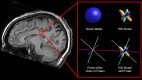

Aging is associated with widespread alterations in cerebral white matter (WM). Most prior studies of age differences in WM have used diffusion tensor imaging (DTI), but typical DTI metrics (e.g., fractional anisotropy; FA) can reflect multiple neurobiological features, making interpretation challenging. Here, we used fixel-based analysis (FBA) to investigate age-related WM differences observed using DTI in a sample of 45 older and 25 younger healthy adults. Age-related FA differences were widespread but were strongly associated with differences in multi-fiber complexity (CX), suggesting that they reflected differences in crossing fibers in addition to structural differences in individual fiber segments. FBA also revealed a frontolimbic locus of age-related effects and provided insights into distinct microstructural changes underlying them. Specifically, age differences in fiber density were prominent in fornix, bilateral anterior internal capsule, forceps minor, body of the corpus callosum, and corticospinal tract, while age differences in fiber cross section were largest in cingulum bundle and forceps minor. These results provide novel insights into specific structural differences underlying major WM differences associated with aging.